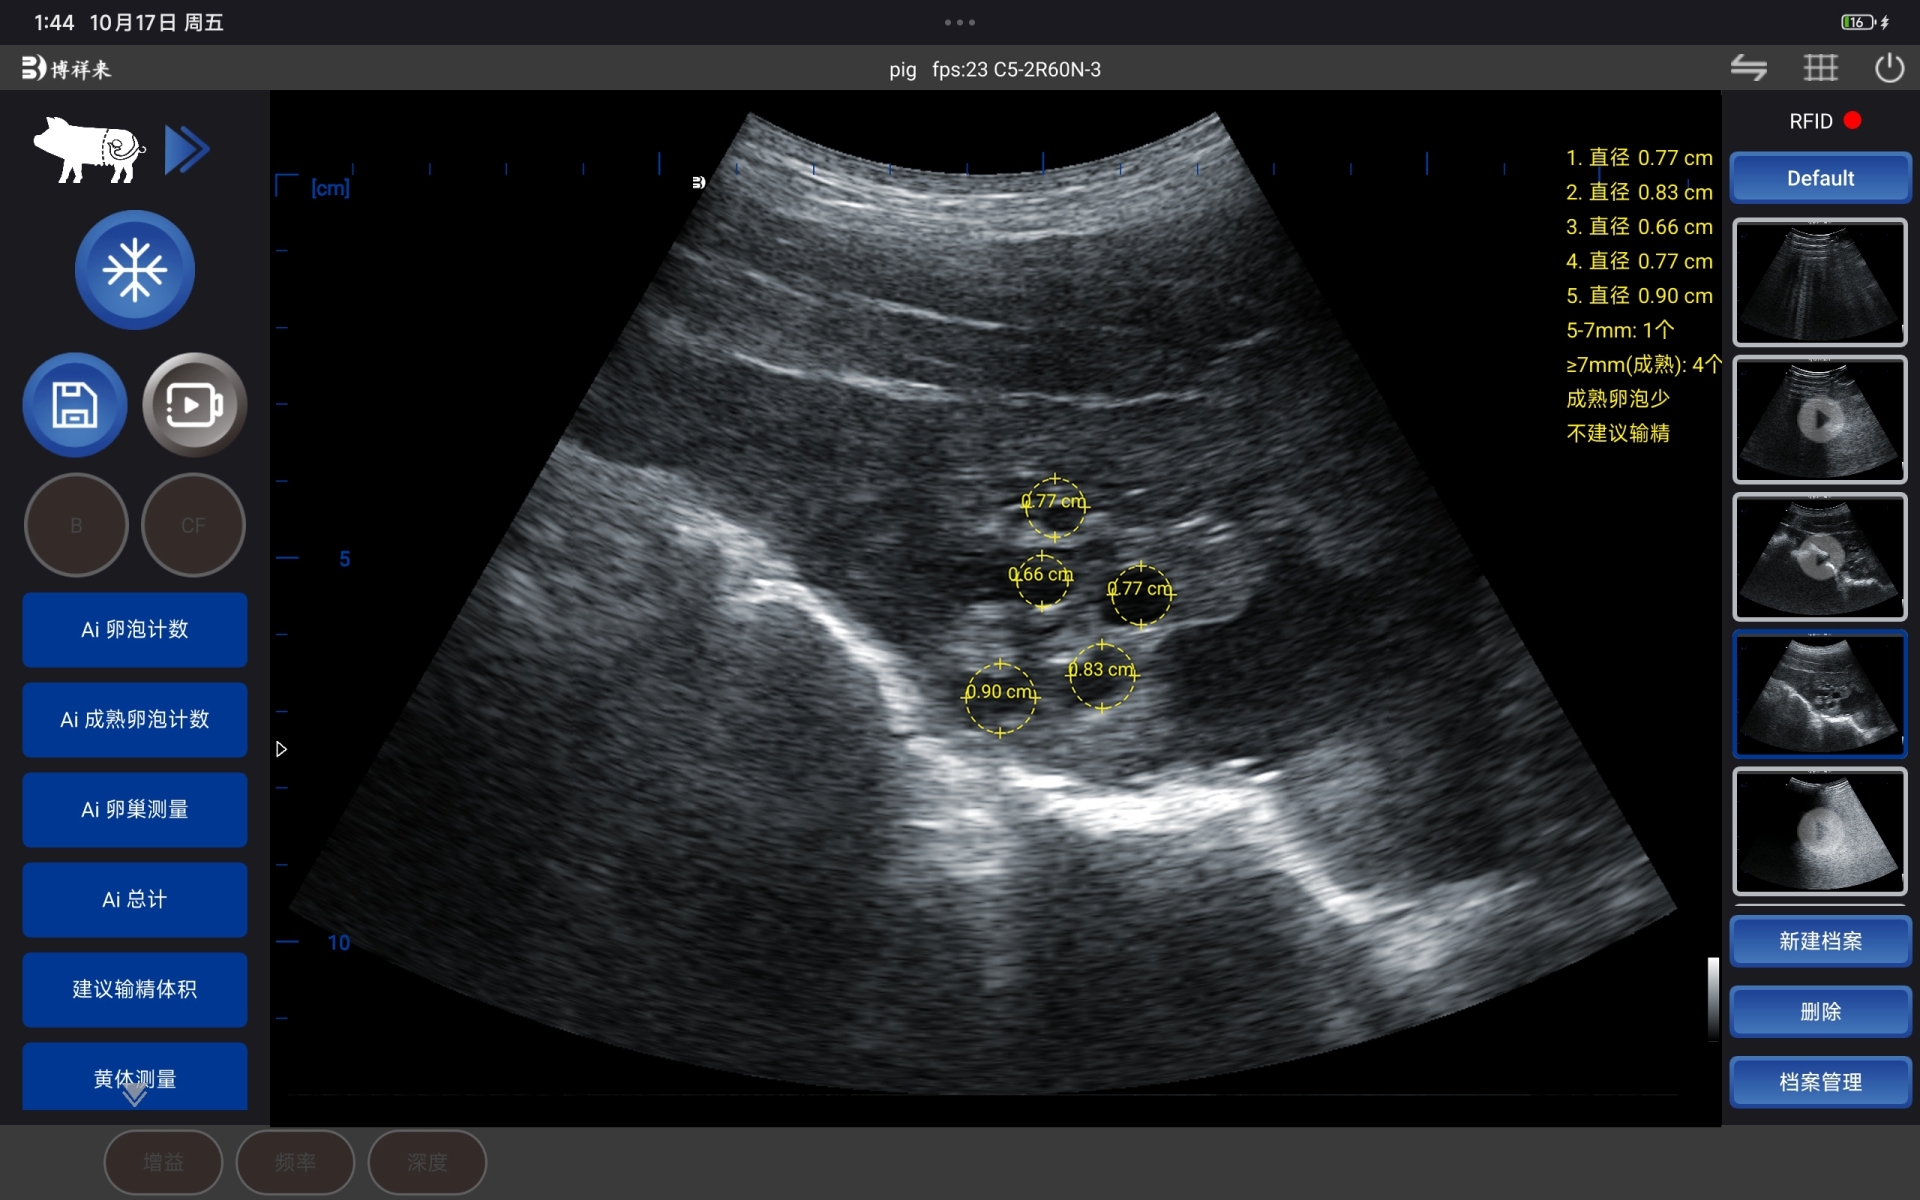

在检测过程中,BXL-S301 猪用B超机针对母猪卵巢特点进行了成像优化,卵泡在屏幕上呈现为:

边界清晰的低回声圆形结构

多个卵泡可在同一视野内同时显示

卵泡与周围组织对比度明显,便于识别

相比传统肉眼判断或单一经验推测,母猪卵泡检测仪通过图像方式,把卵泡状态“看得见、数得清”。

通过 BXL-S301 猪用B超机,结合 AI 卵泡识别技术,